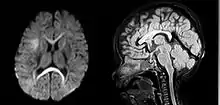

| An MRI of a patient with benign familial macrocephaly (male with head circumference > 60 cm) | |

Macrocephaly is a condition in which circumference of the human head is abnormally large.[1] It may be pathological or harmless, and can be a familial genetic characteristic. People diagnosed with macrocephaly will receive further medical tests to determine whether the syndrome is accompanied by particular disorders. Those with benign or familial macrocephaly are considered to have megalencephaly.

Benign macrocephaly can occur without reason or be inherited by one or both parents (in which it is considered benign familial macrocephaly and is considered megalencephaly form of macrocephaly). Diagnoses for familial macrocephaly is determined by measuring the head circumference of both parents and comparing it to the child's. Benign and familial macrocephaly is not associated with neurological disorders.[2] While benign and familial macrocephaly does not result in neurological disorders, neurodevelopment will still be assessed.